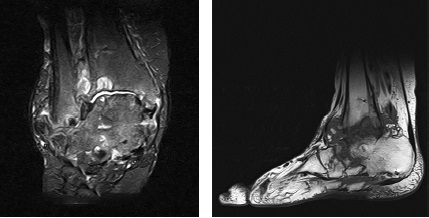

Fig. 4. MRI of the ankle joint. Pronounced swelling of the spongy substance of the talus body, multiple bone cysts of the posterior part of the foot, pronounced paraarticular inflammatory reaction of tissues

Radiological examination methods (radiography, MRI, MSCT of the ankle joint) showed undoubted signs of posttraumatic AVN of the talus and its complications in the form of collapse of the talus, multiple cysts of the tibia, talus, calcaneus, etc. (Fig. 2, 3, 4).